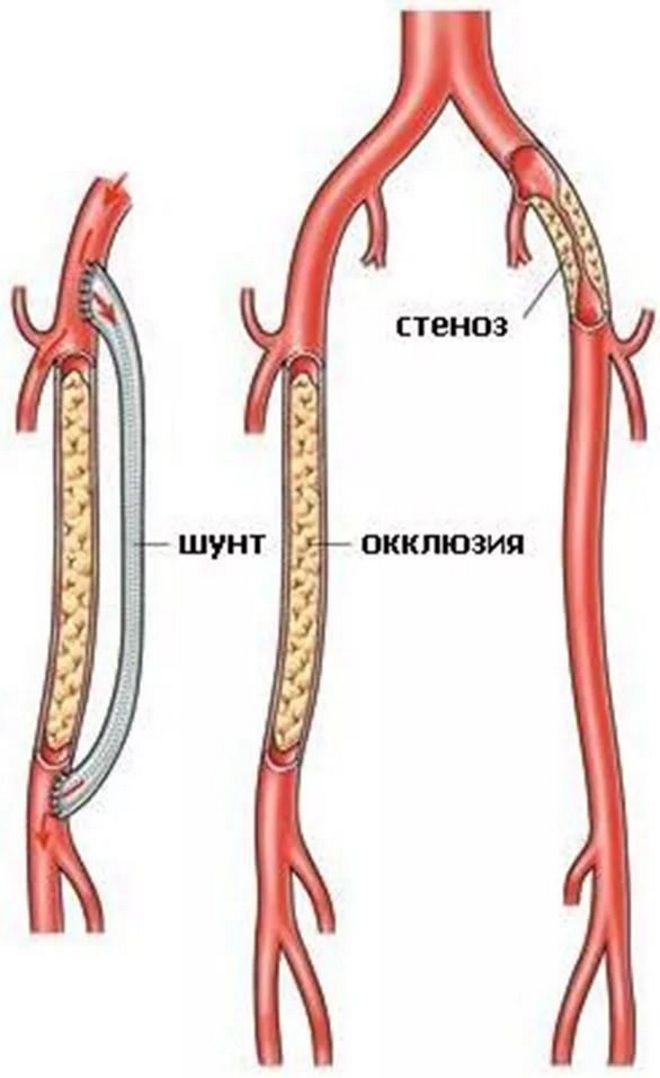

Хроническая окклюзия артерий: причины, симптомы и лечение